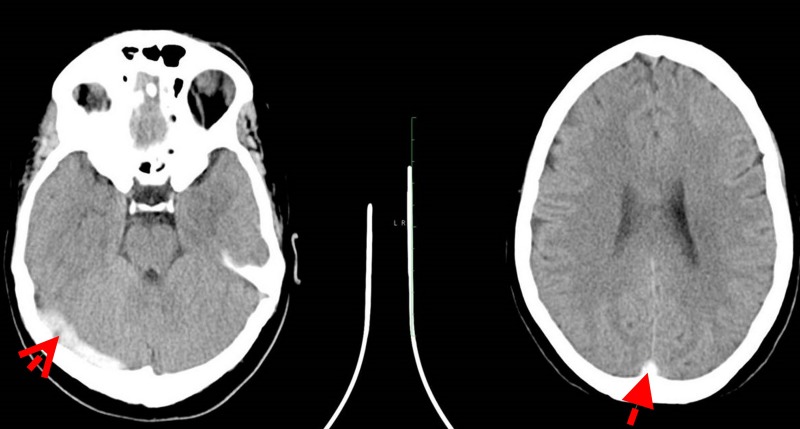

Cerebral Venous aSinus Thrombosis (CVST)

Blood clot formation in the cerebral venous sinuses, which can cause headaches, seizures, stroke, and elevated intracranial pressure. Management involves anticoagulation and, in severe cases, endovascular thrombectomy or thrombolysis. Dr. Choudhri has published on both spontaneous venous thrombosis management and the rare complication of delayed venous thrombosis following fistula treatment.